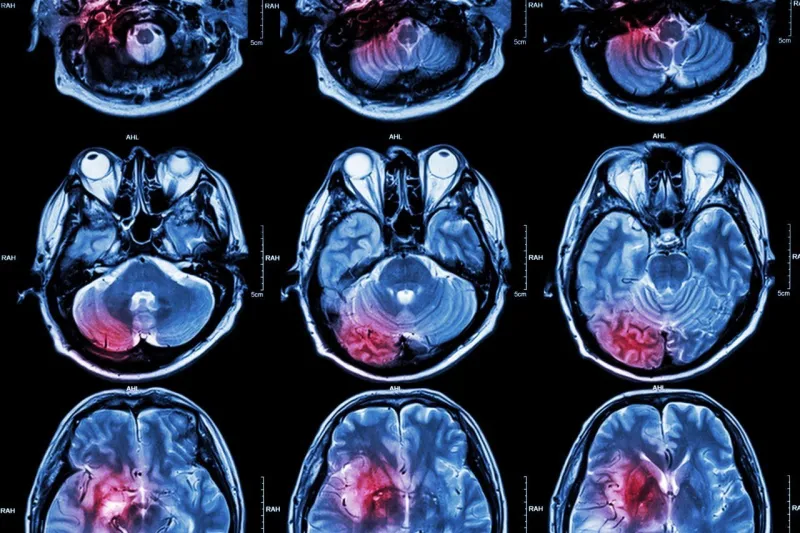

Cancer : 5 idées reçues sur les tumeurs cérébrales

Une tumeur cérébrale survient suite à la multiplication anormale de cellules qui constituent une masse, cancéreuse ou non, dans le cerveau. "Elles effraient la plupart des gens, mais contrairement à ce que vous pensez, elle n'a pas toujours une issue fatale, loin de là", déclare Sean Grimm, MD, un neurologue américain. Il fait le point sur les 5 idées reçues les plus fréquentes concernant la tumeur cérébrale.